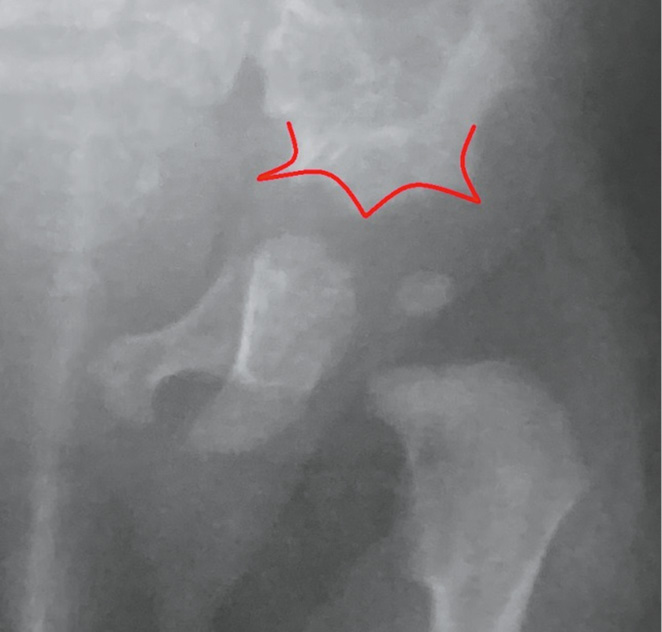

При рентгенографии костей таза у семи пациентов присутствовал типичный «трезубец» вертлужной впадины, образованный срединным выступом и двумя боковыми шпорами. Рентгенологическая картина «трезубца» несколько изменялась в пределах изученной группы пациентов, но в той или иной степени носила достаточно яркий характер. Причиной данного рентгенологического феномена является особенность оссификации надацетабулярной области. В результате неравномерного характера этого процесса на рентгенограммах таза в прямой проекции отчетливо видны три «зубца», при этом медиальный «зубец» очерчен внутренним кортикальным слоем седалищной вырезки и нижним контуром оссифицированной части подвздошной кости, латеральный «зубец» — наружным надацетабулярным контуром оссифицированной части подвздошной кости и сводом вертлужной впадины, а центральный «зубец» — сводом вертлужной впадины и нижним контуром оссифицированной части подвздошной кости (рис. 2). Симптом наблюдался при рождении и был более выражен в младенческом возрасте, в дальнейшем «зубцы» сглаживались по мере оссификации хрящевых элементов вертлужной впадины. Следовательно, при подозрении на ТДКР у детей старшего возраста необходим ретроспективный анализ рентгенограмм тазобедренных суставов, который поможет выявить характерную рентгенологическую картину и обосновать клинико-рентгенологический диагноз для последующего генетического обследования.

Рис. 2. «Симптом трезубца» на рентгенограмме левого тазобедренного сустава у пациента 3 мес. с торакальной дисплазией (выделен красным)